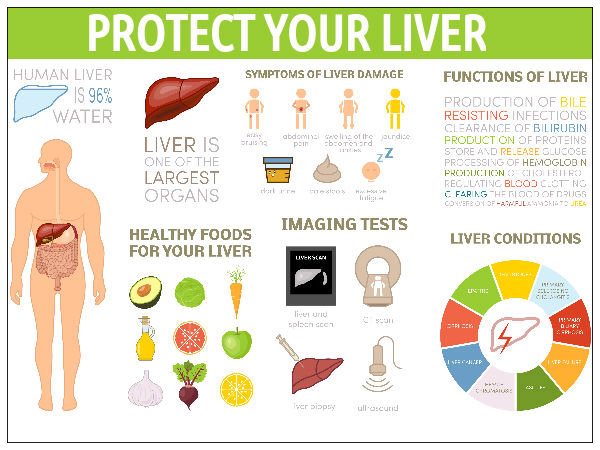

How To Improve Liver Function Boldsky

Liver Health 5 Superb Foods That Helps To Boost Liver Function

Liver Health 5 Superb Foods That Helps To Boost Liver Function